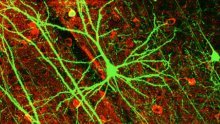

KAP, EPILEPSIJA, METAK...

Otkrivena tehnika koja liječi razne ozljede mozga